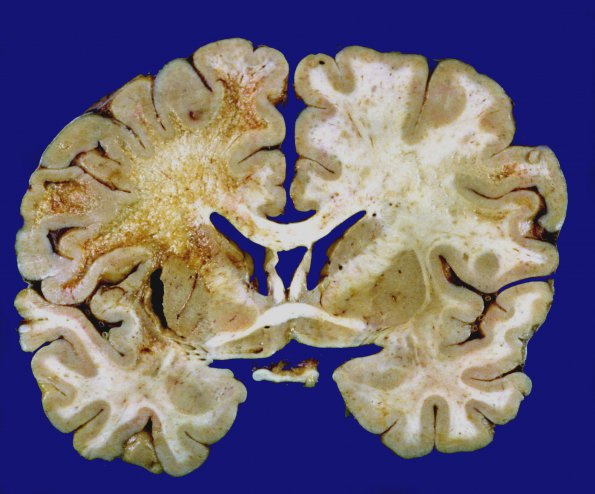

Exceptional example of involvement of the centrum semiovale and the variation of involvement of the left and right hemispheres.